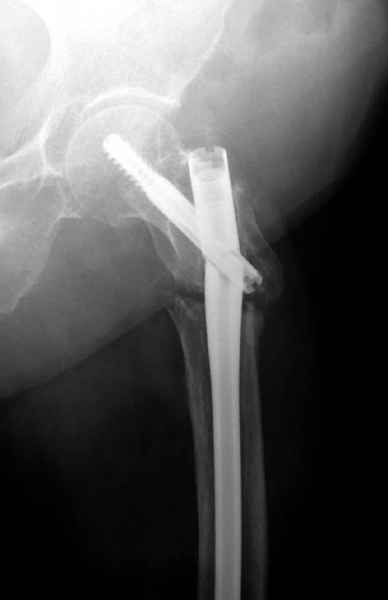

77 летняя больная направлена в нашу клинику на дальнейшее лечение. Из истории, травму получила в сентябре 2007 года и по поводу перелома шейки бедра больная была проперирована тремя каннюлированными шурупами с явным нарушением технологии установки шурупов. Внизу вместо одного шурупа имеется два, что привело к стрессу латерального кортекса. Через месяц по поводу ятрогенного подвертельного перелома сделана фиксация длинной Гамма 3. Установлен без проксимальной блокировки? (set screw). В данный момент имеется несостоятельность конструкции и ложный сустав. Передвигается с помошью костылей, конечность укорочена на 2 см. Какие будут рекомендации?Djoldas Kuldjanov, MDDepartment of Orthopedic SurgerySt. Louis University Medical Center